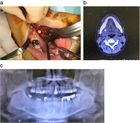

1. 唾石に伴う口底の発赤、腫脹および疼痛がある場合、抗生剤、抗炎症鎮痛剤を投与することが推奨される(推奨度1)

1. 口底に限局した導管内前方部唾石の診断に対し、咬合法X線画像検査が推奨される(推奨度2)

1. 導管内に限局し比較的小さいものでは唾液腺マッサージし自然排出を促すことが推奨される(推奨度2)